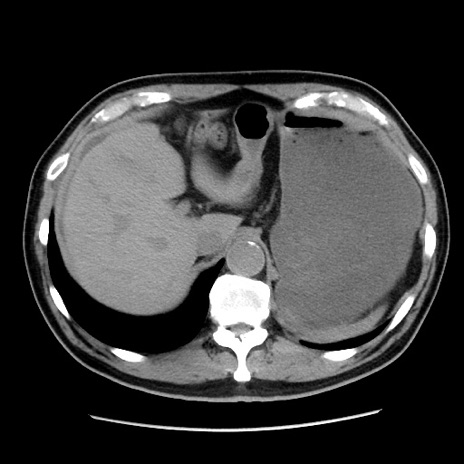

症例16(横断像)

【症例】 70歳代男性

【主訴】 腹痛、嘔吐

【現病歴】 約1ヶ月前より間欠的に腹痛と嘔吐あり、当院消化器内科を受診したところCTで多発する肝臓のLDAを指摘され、精査中であった。以降は消化器症状は安定していたが、2日前より嘔気と腹痛があり、同日より排便・排ガスが消失した。改善認めず、 本日、救急外来を受診した。

【既往歴】 大腸ポリープ切除後。

【身体所見】意識清明・会話良好、BT 36.3℃、BP 127/80mmHg、 P 80bpm、腹部:膨満あり、平坦・軟、上腹部正中および下腹部正中に圧痛あり、反跳痛なし、筋性防御なし。

【データ】WBC 7200、CRP 0.77